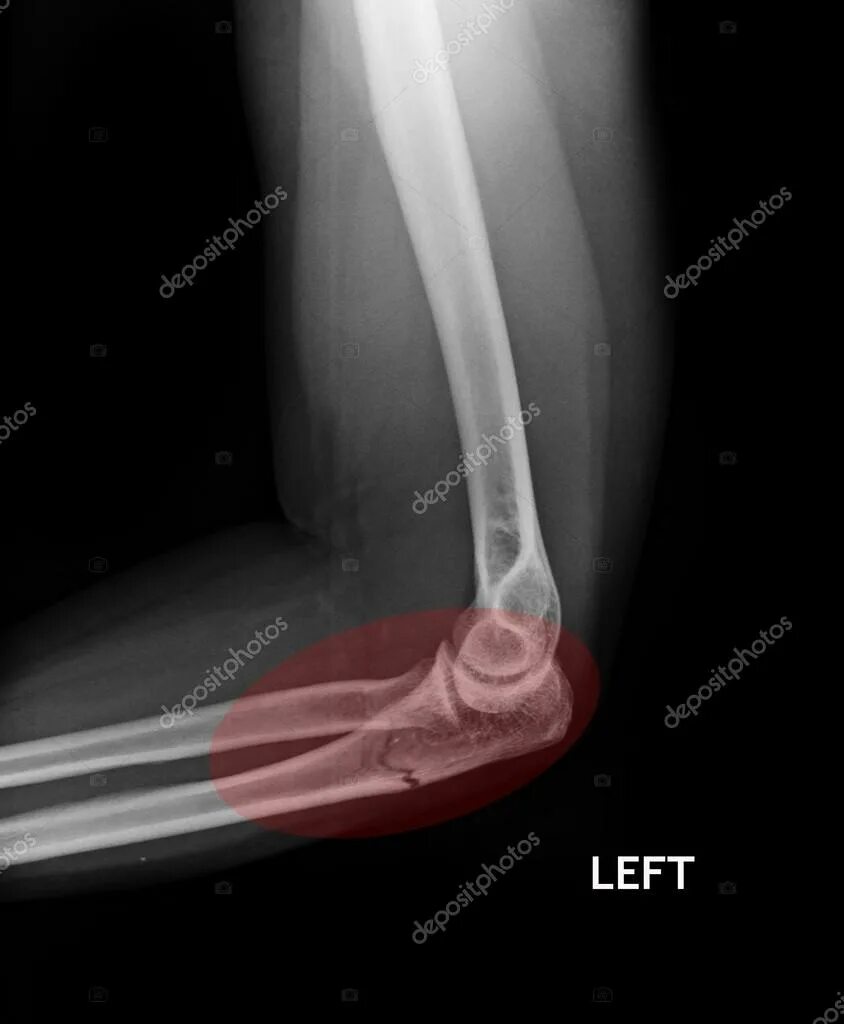

Перелом смещение локтя